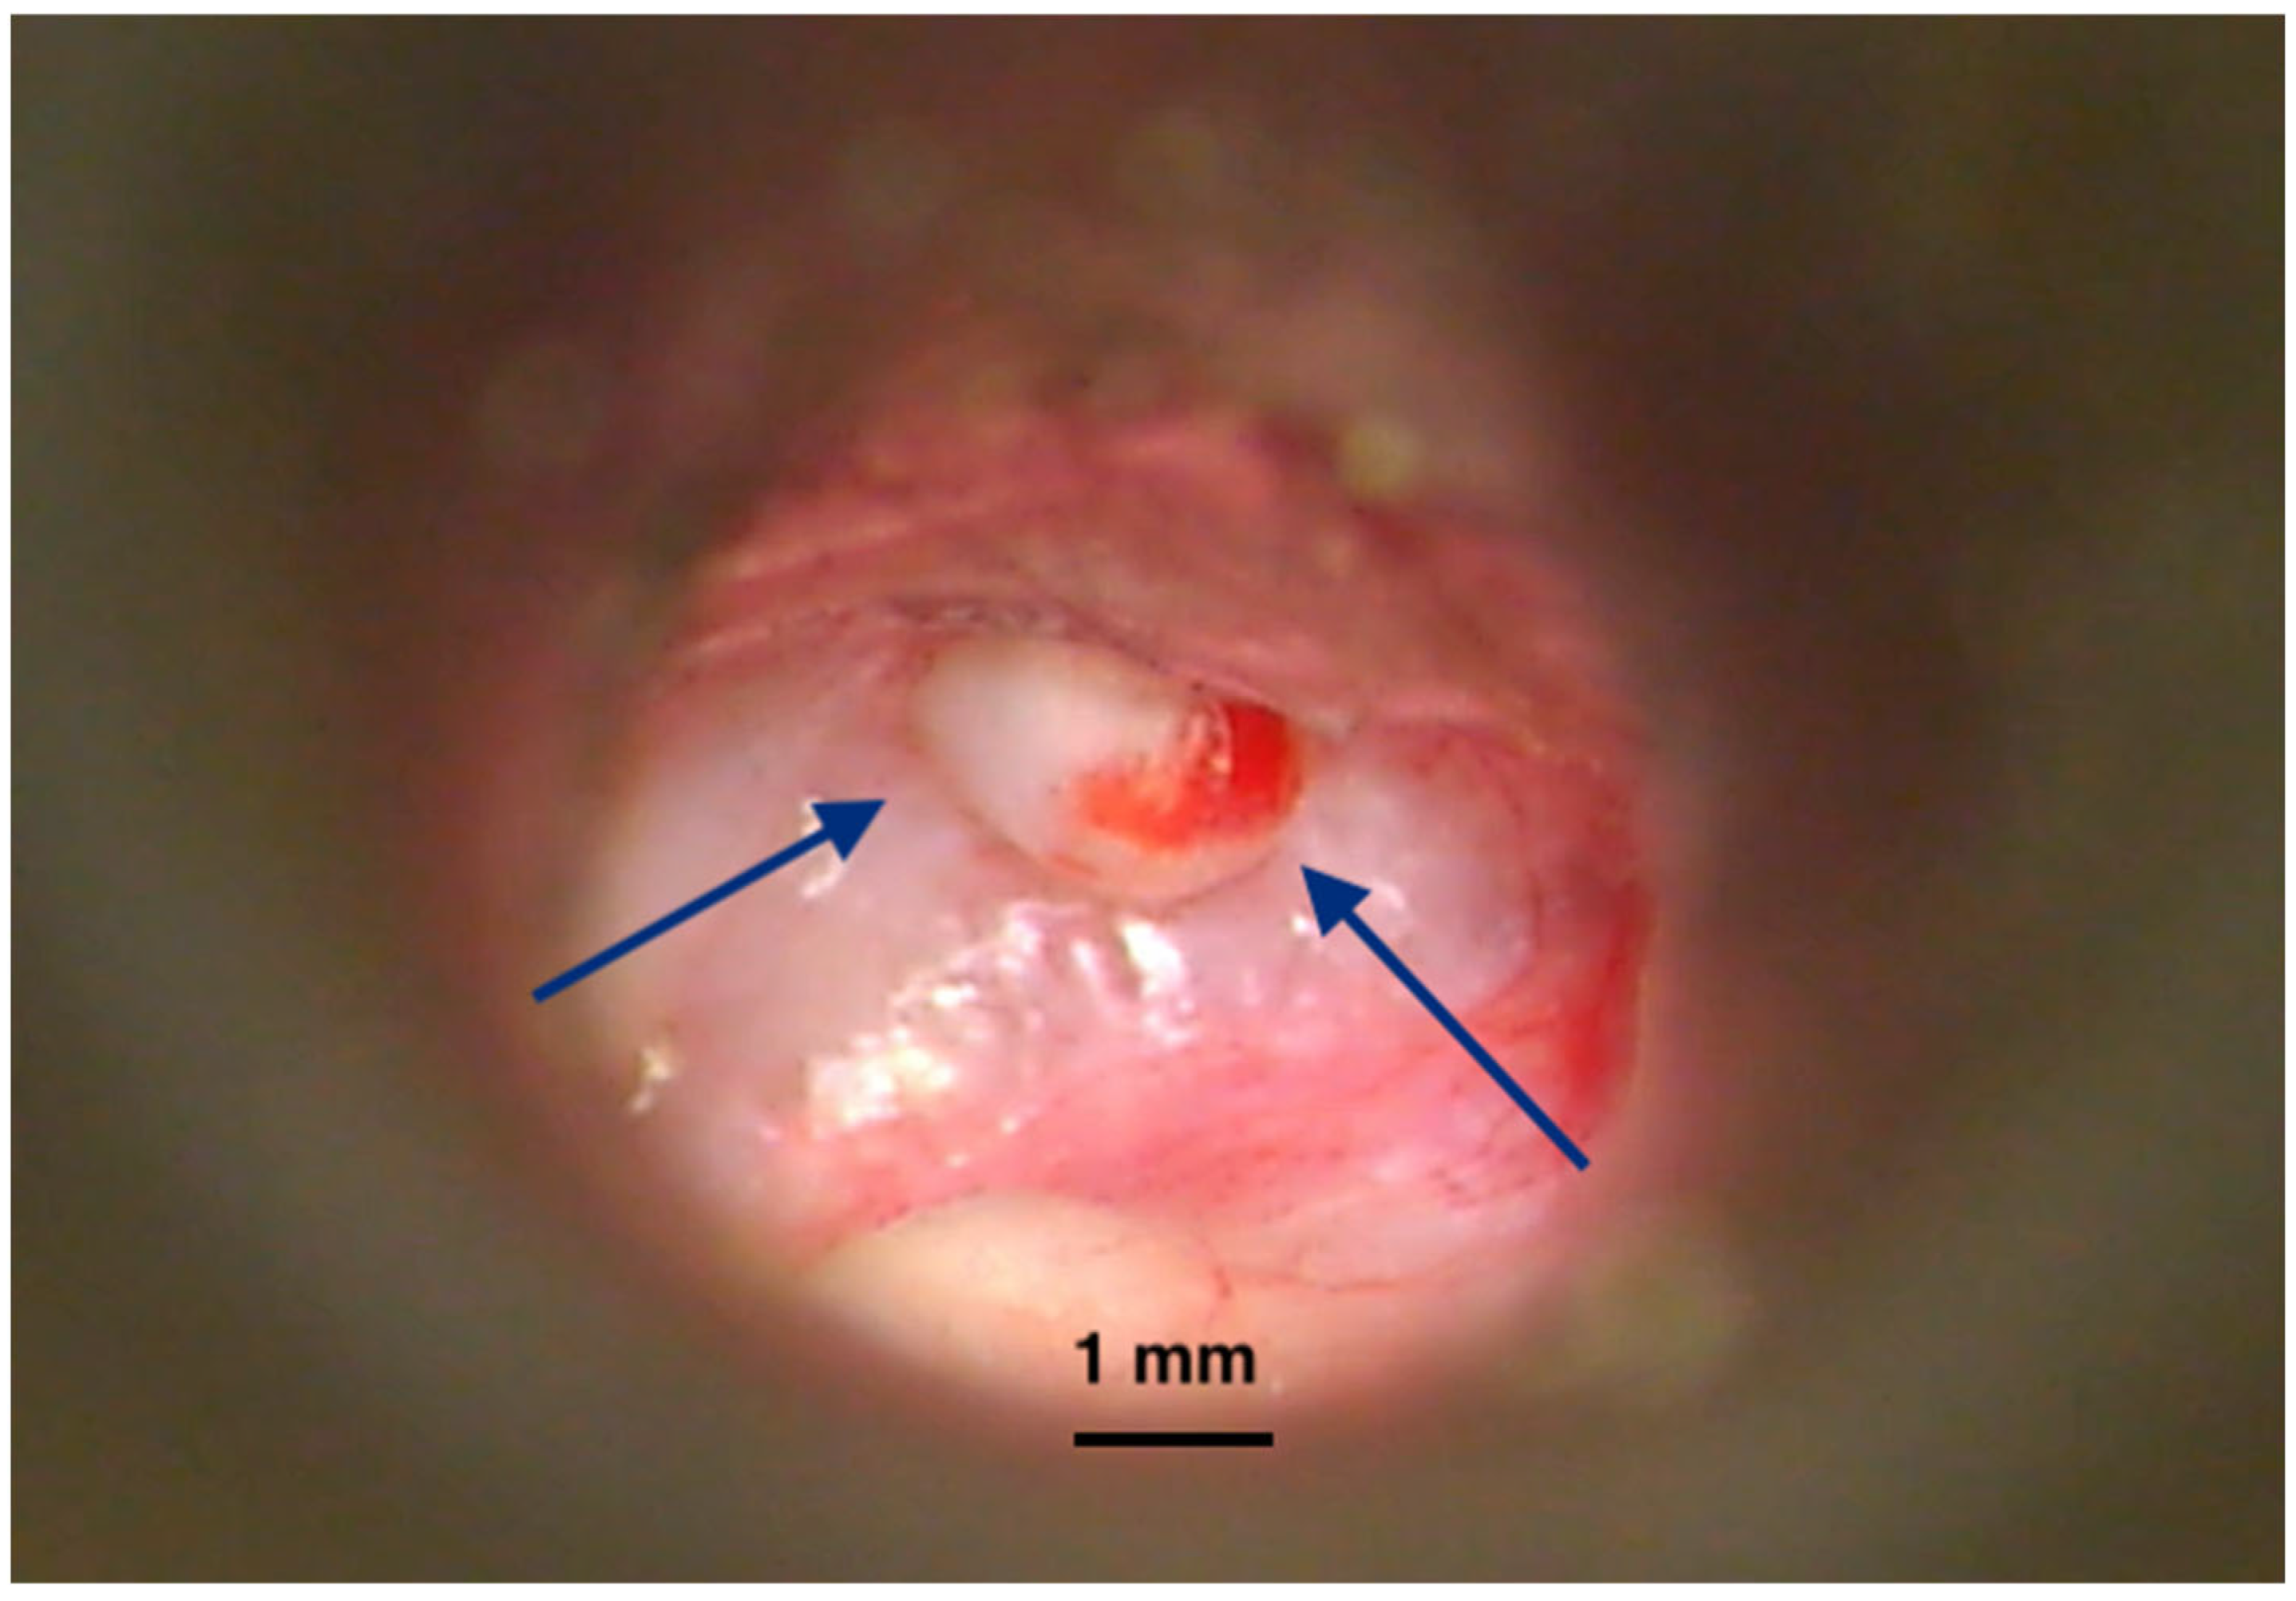

The time between surgical removal and disease recurrence can vary greatly; hence, continuous monitoring over the long term is required [16,17]. Since only clinical examinations and imaging (MRI) are useful in this regard, medical resources and financial burden are critical for this disease. The statistics report a more aggressive disease in children [14]. In addition, due to their longer life span, more active diagnosis and management protocols are required. There have been many publications reporting the risk factors for local recurrence. Different locations of the disease within the temporal bone have been reported with varying rates of residual/recurrent lesions (Figure 3), leading to an extensive classification and staging of the cholesteatoma [18]. Surgery of the middle ear (e.g., ventilating tubes, cochlear implants) could also explain the genesis of a small number of cholesteatoma cases inside the tympanic and mastoid cavities [19,20,21].

Figure 2. Acquired cholesteatoma. Intraoperative image of surgery for an acquired cholesteatoma on the left ear. Epithelial matrix covered with keratin debris is visible on the inner wall of the middle ear and mastoid cavities. Bone erosions can be observed at the periphery of the lesion, suggesting the mechanism of invasion inside tympanomastoid spaces. (TM—Tympanic membrane, FN—facial nerve, LSC—Lateral semicircular canal). Picture taken with Zeiss TIVATO 700 microscope (ZEISS Microscopy, Jena, Germany). (from D.C.G’s. personal collection).